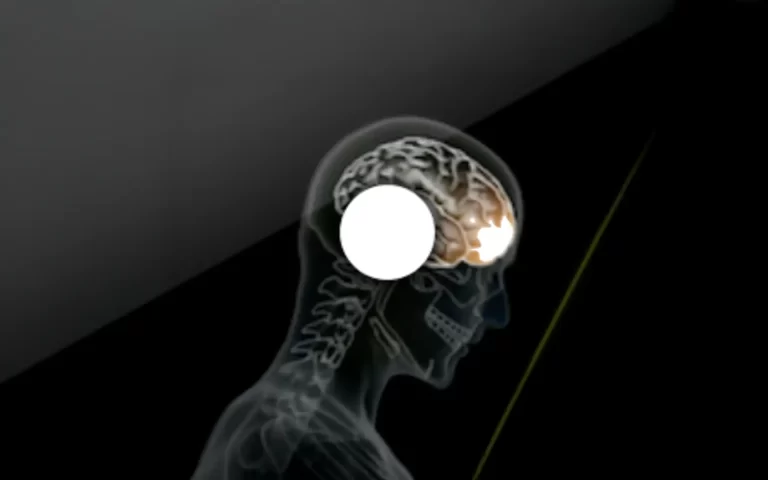

Mouthguards and Concussions: Unpacking the connection

Mouthguards protect teeth, not brains. Learn why they don’t prevent concussions, but still play a key role in contact sports safety and injury awareness.